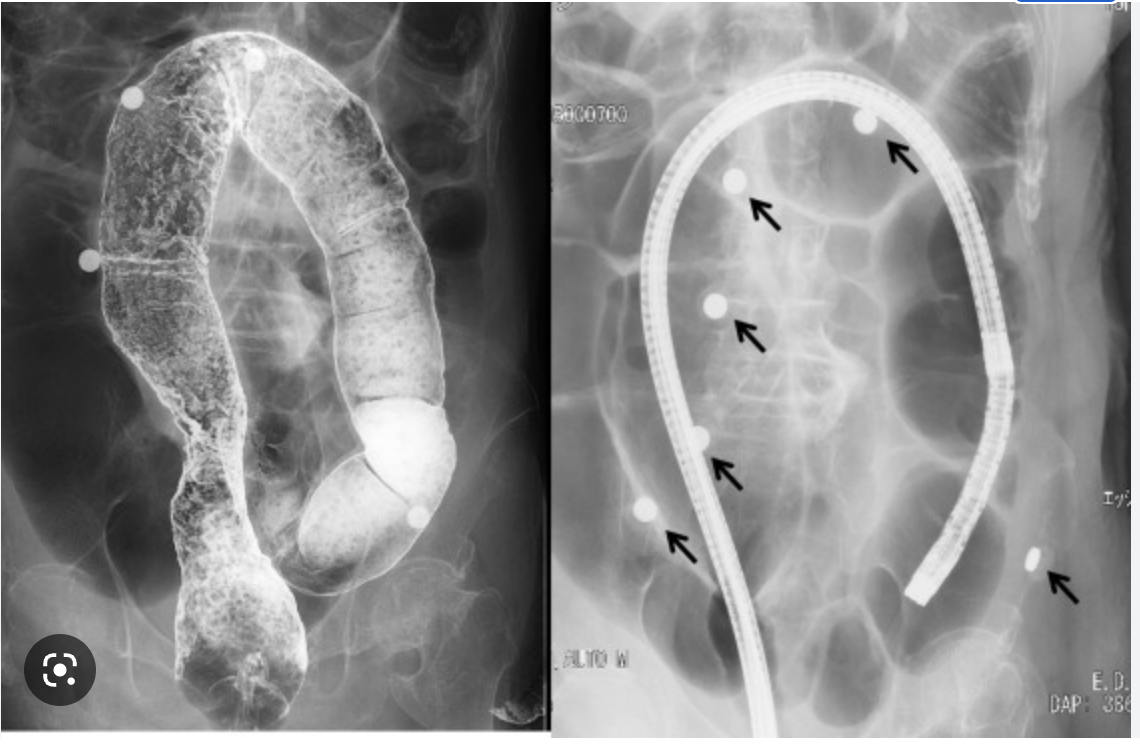

2 of the main types of volvulus are sigmoid and cecal. We can tell which is which on a an X-ray. Out of sigmoid and cecal, which is associated with:

• coffee bean sign

• caecal embryo sign

A

• coffee bean sign = sigmoid

• caecal embryo sign = caecal